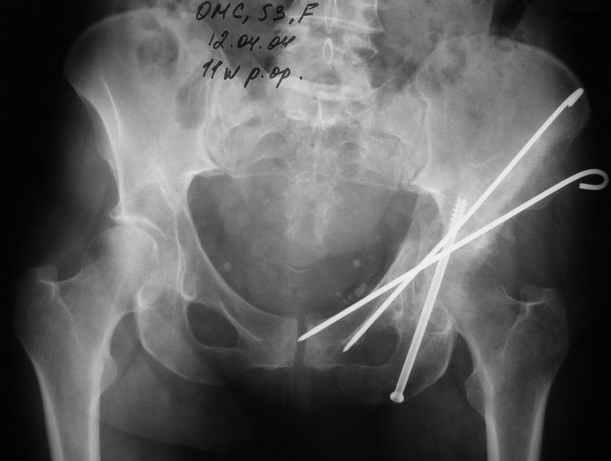

Однако есть альтернатива. Репозиция из подвздошного доступа тазовыми щипцами с разнодлинными браншами или тазовым пистолетом, а фиксация задней колонны через седалищный бугор или тазрвыми винтами 4,5 или каннюлированными 6,5 или 7,3. По-моему я посылал на ортофорум такой снимок, когда жаловался на ишемический неврит седалищного нерва через сутки после операции. Не забудь про шейку бедра - мне кажется будет хорош длинный PFN любой фирмы, какую ты найдешь, а нет так UFN + miss a nail, как это здорово делают мои земляки - Ебурбуки. Пока.

12.04.04